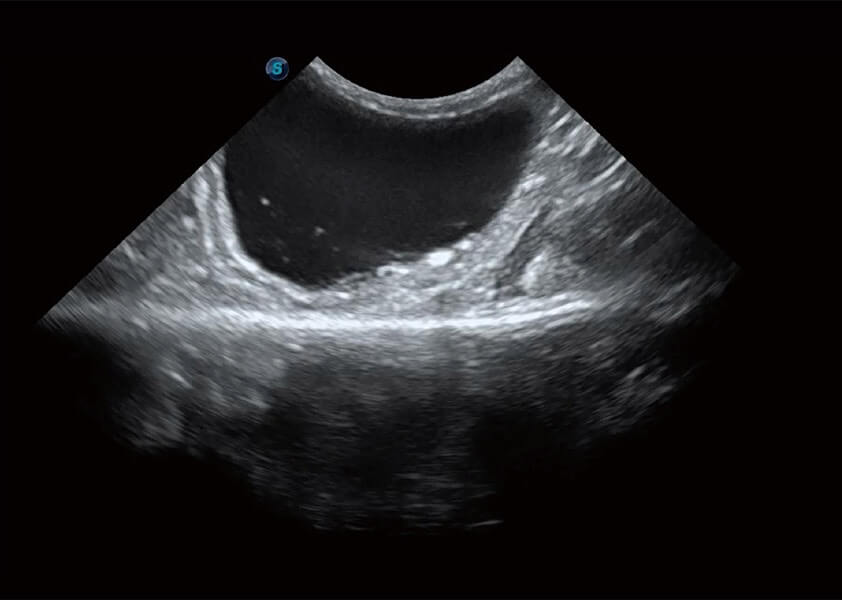

(犬)胆囊泥沙

(猫)膀胱结晶

(犬)乳头肌短轴